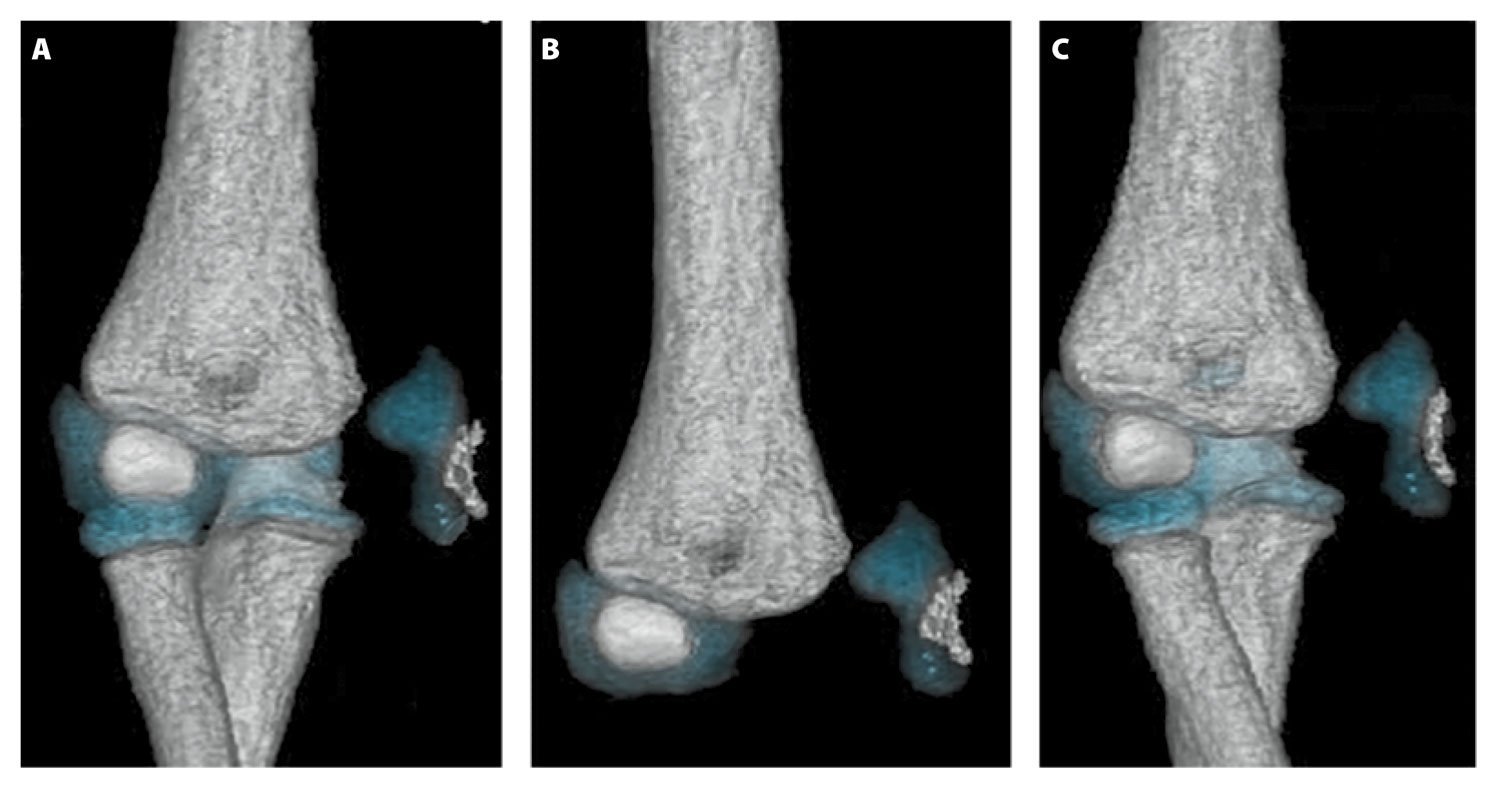

MR images revealed an avulsion fracture of the right medial condyle and epicondyle. The fragment was displaced medially and rotated; the articular surface was oriented laterally facing the distal humerus, which correlated with the calcification seen on previous radiographs. The displaced, predominately cartilaginous, trochlear and medial epicondyle fracture fragment was visible on cartilage-specific fat-suppressed T1 volume sequences (see Figure 3). MR images were sent to the 3-D Innovation Laboratory and processed into 3-D volume-rendered images for surgical planning using a sequence that isolates bone and cartilage from adjacent structures. Orthopedic surgeons evaluated the images, and determined that an open reduction and internal fixation surgical procedure was required. They performed the procedure on the trochlea and medial epicondyle, using Kirschner wires to repair the fracture. A postoperative radiograph, obtained while the elbow was in a cast, showed Kirschner wire placement and confirmed fracture repair (see Figure 4).

Multiplanar multisequence MR imaging of the right elbow, without gadolinium contrast, was performed with the patient under general anesthesia after several radiographic examinations led to incorrect diagnoses. A 3-D fat-suppressed T1 gradient echo sequence was used to capture volumetric image data and highlight cartilage and bony anatomy. The data were sent to the 3-D Innovation Lab for postprocessing, and technologists used Smart Segmentation (CT Viewer, Intellispace Portal, Philips) techniques, which involved highlighting individual anatomical parts of the elbow and combining them into a 3-D volumetric image. The segmentation tool provides a method to manually segment each part of the anatomy and assign colors to each tissue so that bone and cartilage are easily identified. The 3-D view of the fracture and cartilage revealed their relationship to the displaced osteocartilaginous fracture fragment, which was useful for the radiologist reviewing the MR images as well as for the orthopedic surgeon (see Figure 5). 3-D volume sequences have been used for some time to create coronal, axial, or sagittal reformats from source data. However, the use of 3-D volume sequences to make 3-D volumetric images in musculoskeletal imaging is a new application.

Figure 5.3-D volume renderings of the right elbow, demonstrating a displaced osteocartilaginous medial condyle and epidondyle fracture fragment along the medial aspect of the elbow joint. Images courtesy of the authors